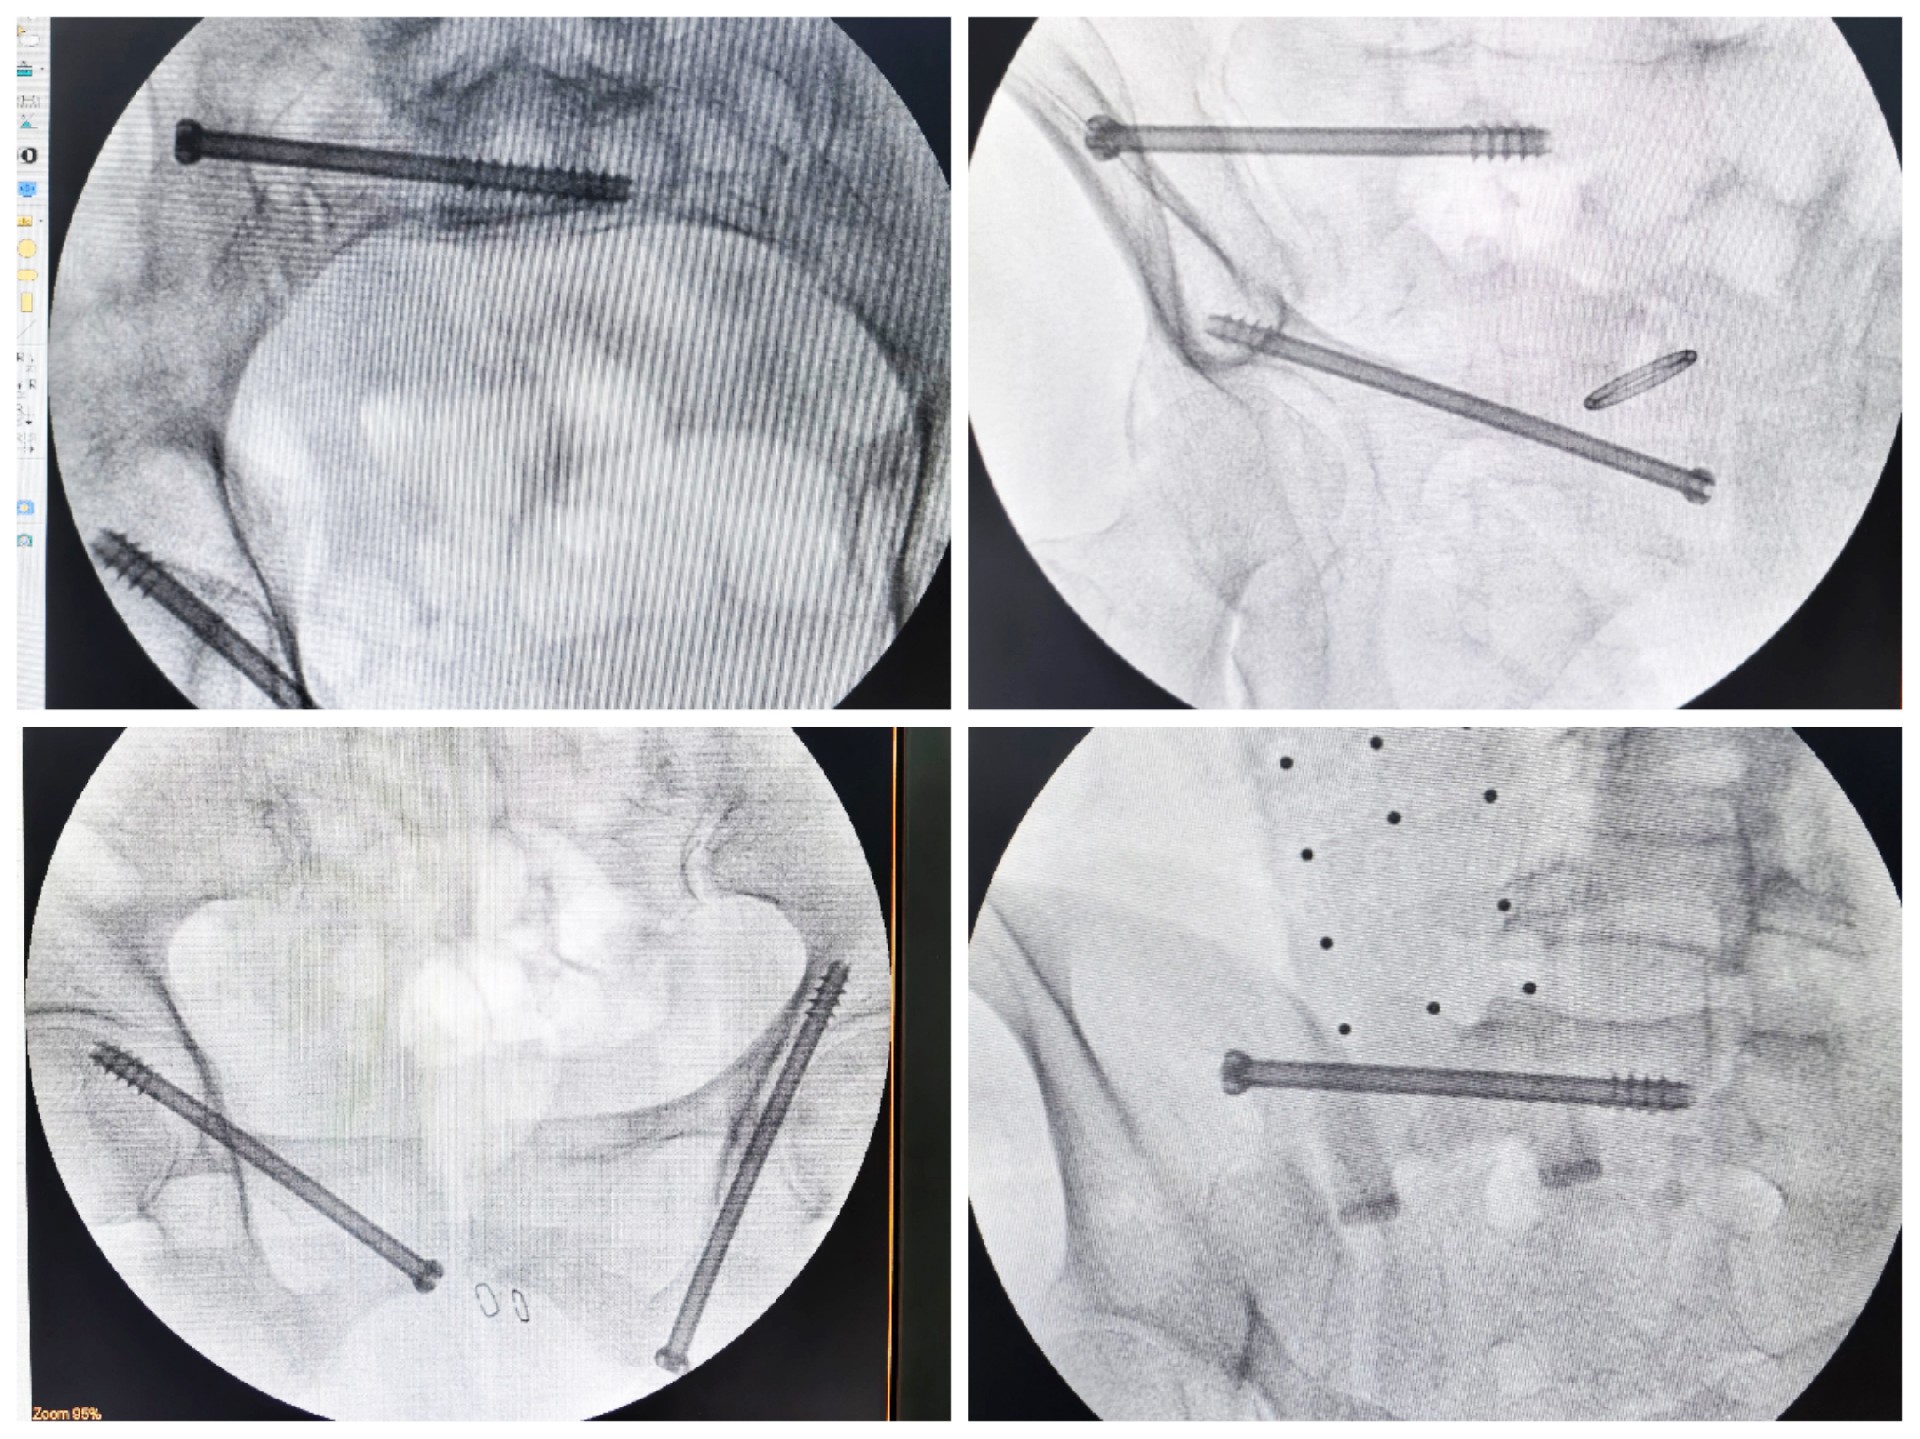

近日,我院骨創外科二病區團隊在宋華科主任的帶領下,在手術室和麻醉科的通力配合下,完成十余例HoloSight知見創傷骨科機器人輔助下骨盆骨折精準微創手術。

傳統的骨盆骨折微創手術中,骶髂螺釘等螺釘置入的難點在于骨盆部位解剖十分復雜,螺釘置入如有偏差極易損傷重要神經及血管,手術不僅依靠手術醫師豐富的經驗,還需要術中反復的C型臂透視及調整,對患者及醫生都有較大輻射。而利用HoloSight知見創傷骨科機器人進行骨盆骨折微創手術,通過高精度光學定位追蹤技術與混合現實技術,使整個微創手術全程可視化,可以在電腦屏幕上實時顯示螺釘的精準置入位置,降低手術風險,提高手術效率及安全性。

術前,手術團隊認真分析討論病例,全面掌握骨盆骨折微創治療的關鍵技術,提前設計手術方案并反復模擬演練手術過程。術中,利用HoloSight知見創傷骨科機器人規劃骨折復位方案及定位螺釘通道,實現精準微創手術。手術通過不足1cm小切口完成,最大程度地減少了術中出血,術中幾乎都是一次性成功精準微創地置入內固定螺釘,減少了醫源性操作對骨折周圍骨質的影響,實現骨折微創固定的同時盡可能提高骨折固定的穩定性,為術后患者的快速康復創造了有利條件。